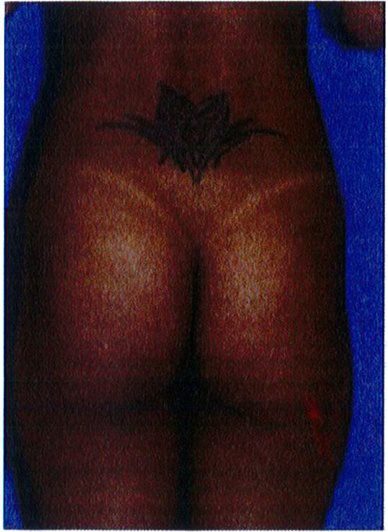

Bởi trên cùng của cơ mông phải vượt qua khoảng ¼ đến 1/ 3 đường cong tính từ vị trí điểm cao nhất của đường liên mông. Nếu bờ cơ mông hoặc vùng V không được xác định rõ, mông trông sẽ bị dẹt, không căng tròn. Để cải thiện vùng V, hãy đánh giá xem vấn đề dẹt là do thừa mỡ hay thiếu thể tích mông, hoặc cả hai. Để từ đó quyết định xem nên hút mỡ hay nâng mông bằng implant hoặc ghép mô mỡ, hoặc cả hai.

Trong vùng mông trên, phần tiếp giáp giữa đường liên mông và tam giác cùng phải là một hình chữ V lõm sâu vào trong. Vùng này được gọi là vùng chữ V.

Vùng này lõm vào bao nhiêu sẽ ảnh hưởng tích cực đến tính thẩm mỹ bấy nhiêu. Nếu lý tưởng, bờ các khối cơ mông phải dễ dàng xác định được bằng cách sờ ở phía bên ngoài, với hình dạng bán nguyệt cong lên trên (Hình 21).

Hình. 21. Đánh giá mối tương quan giữa cơ mông và vùng trên trong mông và tam giác cùng. Ở ảnh bên trái, điểm chấm đen là khớp gian đốt L5-S1, đường nét liền phía dưới đành dấu điểm cuối cùng của đường liên mông, và đường chấm đánh dấu điểm cuối cùng của bờ trên cơ mông lớn. Bệnh nhân ở phía bên trái có thể thấy rõ vùng chữ V cũng như bờ cơ mông lớn. Bệnh nhân bên phải không thấy vùng chữ V vì thiếu thể tích vùng mông cũng như thừa mỡ vùng V, vì thế trông mông sẽ bị det.